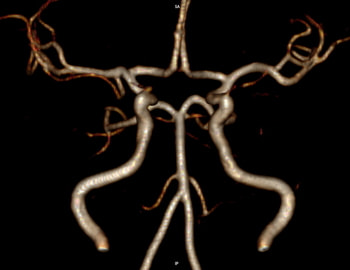

最初に問診を行います。必要に応じて検査を行い、その後、診察/検査結果を説明し方針を立てます。脳神経外科診療においてはMRI検査が頭蓋内評価に有用ですので、診察/診断の根拠のためにもキー写真をスナップショットでお渡しするようにしております。

頭痛/めまいなどは脳卒中や脳腫瘍などの初発症状のこともるため、MRIにて頭蓋内スクリーニングを行います。当日、結果説明します【理念2・4】。

既に脳梗塞など患った患者に対し、今後の予防や症状悪化を防ぐため生活習慣病指導を行います【理念1・2】。また、必要に応じ麻痺の維持改善目的で経頭蓋磁気刺激療法を積極的に取り入れております。【理念1】。